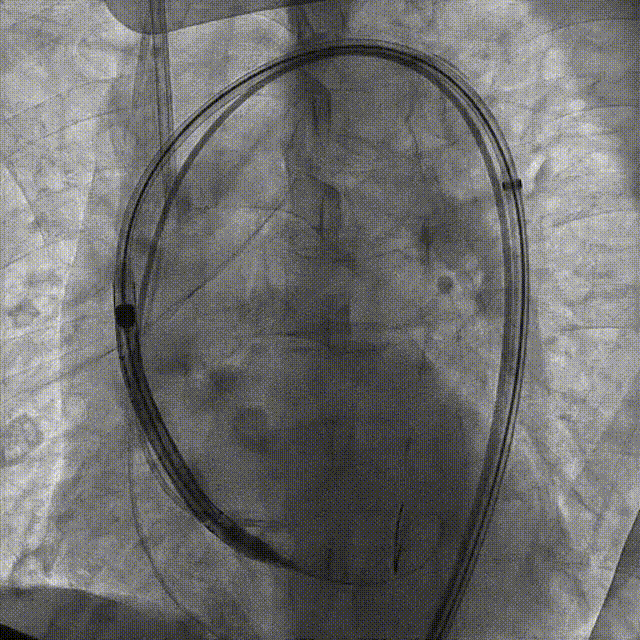

刘煜昊教授 阜外华中心血管病医院(点击查看专家详细简历) 首瓣选耐久,干瓣护航全生命周期管理 2025年ESC专家共识里指出:“推荐第一个瓣膜要选经证实具有长期耐用性的外科瓣膜与经导管瓣膜,以降低再次介入治疗的可能性 ,对于瓣环较小、根据预测有效瓣口面积(EOA)评估存在严重 PPM 风险的患者,可采用主动脉根部扩大术联合 SAVR,或植入环上瓣,对于小瓣环患者自展瓣拥有比较好的血流动力学优势”。 每一次术前评估,都是我们与患者携手面对未知的起点。我们始终以患者全生命周期获益为核心,在瓣膜选择与术式规划中,不只着眼于当下解剖适配,综合评估解剖条件、预期寿命与生活质量。从年轻患者到高龄人群,瓣膜耐久性与血流动力学稳定性始终是决策核心! 陈同峰教授 阜外华中心血管病医院(点击查看专家详细简历) 医学的进步正不断拓宽生命的边界,每一次术前评估都是对生命尊严的深度凝视,技术与人文的交融,让风险不再仅是数字的堆叠,而是成为医者与患者共同面对未知的勇气见证。术中瓣膜释放结束,到了导管测压的时候,我惊喜:瓣膜不错啊,压差为0,这不仅仅得益于瓣膜形态的设计,更是环上瓣及瓣叶材质优质的体现,感受到了 Prostyle A瓣膜在血流动力学上的卓越表现,其采用的抗钙化处理技术有效延长了瓣膜的耐久性,为患者长期生存提供了更可靠的保障。 患者病史 主诉:心慌半月; 门急诊诊断:心悸,冠状动脉粥样硬化性心脏病,心脏瓣膜病,主动脉瓣狭窄,高血压,甲状腺术后; 现病史:半月前无明显诱因出现心慌,呈间断性,伴心悸、出汗,伴头晕,无咳嗽、咳痰,无恶心、呕吐,无双下肢水肿,无放射痛及意识障碍,休息约几分钟后可自行缓解,症状反复发作,遂来我院就诊。 术前超声提示:室间隔增厚;主动脉瓣退行性变并重度狭窄;升主动脉明显增宽;室间隔增厚。 术前CT 三叶瓣,轻度钙化集中在无窦和左窦瓣叶边缘,主动脉根部直径19.3mm,LVOT直径17.7mm,LVOT向下收窄; 窦部正常,VTC空间足够,冠脉风险低; 左室腔小,收缩末径20-25mm,“自杀左室”,循环崩溃风险高;主动脉瓣环水平夹角71.1°,横位心,过弓和跨瓣存在一定困难,备snare。 外周双侧入路内径可,双侧入路能够支持20F大鞘通过,右股低分叉。 手术策略 推荐右侧股动脉为主入路,左侧为辅助入路,右股分叉上方1cm穿刺;推荐选择AV23瓣膜,18mm球囊预扩,左右重叠位:LAO 7° CAU 35°;左冠切线位:LAO 27° CRA 16°;右窦居中位:LAO 18° CAU 9°;备Snare,建议ECMO/CPB湿备,术前术中积极补液,警惕循环崩溃风险。 手术过程 在右股动脉穿刺建立通路后,顺利送入大鞘,经食道超声及血管造影确认路径稳定。18mm球囊预扩过程中,患者血压一度下降,迅速完成扩张并立即植入AV23 ProStyle A®瓣膜。瓣膜精准释放于目标位置,超声显示无明显反流及瓣周漏,血流动力学即刻改善。 主动脉根部造影 18mm球囊预扩少量反流 输送系统柔顺跨瓣 精准定位 平稳释放 80%工作位观索位置合适 释放后导管测压,压差由术前53mmHg降为0mmHg 最终造影瓣膜位置形态良好,冠脉灌注良好,无明显瓣周漏 ProStyle A®预装干瓣——助力临床最优化解决方案: 轻松过弓,精准可控:该病例为横位心,在未使用snare的情况下,过弓和跨瓣柔顺,较细的尺寸+柔顺的输送系统通过性能得到了很好的验证; 平衡的收腰设计:该病例瓣环较小且左室腔小,AV23瓣膜的平衡收腰设计既确保了锚定安全性,又保证了EOA,有效降低了循环崩溃风险,而术后0mmHg的压差的表现更加证明了优秀的血流动力学,提高了瓣膜的耐久性; 预装干瓣 便捷顺安:金仕生物专利抗钙化技术运用纳米技术去除组织内的细胞碎片和磷脂,封闭游离醛基,从根本上阻断了瓣膜钙化的多项因素,显著提升了瓣膜的耐久性;同时,相比较传统戊二醛保存方式,干式存储最大限度的保留心包的亲水亲油平衡,还原组织天然曲柔性,进一步保障了瓣叶开合,保证长期耐久性。 专家简介 王小虎 阜外华中心血管病医院(点击查看专家详细简历) 陈冲 阜外华中心血管病医院(点击查看专家详细简历) 赵一品 阜外华中心血管病医院(点击查看专家详细简历)